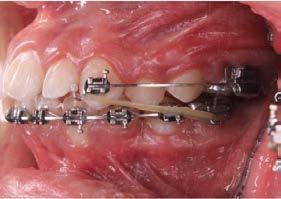

Por lo que se propone procedimiento quirúrgico con la evidente comunicación oroantral al realizar las extracciones de los órganos dentales involucrados. Previa asepsia y antisepsia, colocación de campos estériles, extracción de segundo y tercer molar superior derecho e incisión envolvente con descarga mesial (Figura 3), rotación y afronte mediante puntos simples de la bola adiposa de Bichat para el cierre de la comunicación oroantral (Figura 4), farmacoterapia con base en amoxicilina con ácido clavulánico. Una semana después refiere no presentar rinorrea y mejoría al 100% de la obstrucción. Posterior a 6 meses de evolución clínica (Figura 5) y radiográficamente (Figura 6), no se observa comunicación oroantral o paso de líquidos de la cavidad oral a la cavidad nasal.

4. Cierre de comunicación con la bola adiposa de Bichat.

Figura 3. Colgajo envolvente con liberatriz mesial y alveolo postextracción.